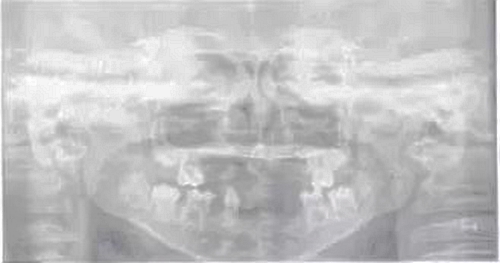

頜面斷層檢查:運(yùn)用數(shù)字放射影像技術(shù)評(píng)估患者缺牙區(qū)牙槽嵴和下頜骨解剖狀況,追問(wèn)病史,患兒家長(zhǎng)否認(rèn)近親結(jié)婚史及家族史。診斷為:(1)小兒軟骨外胚層發(fā)育不全綜合征;(2)牙列缺損。就診后,行全面口腔檢查,取模,制作研究模型。經(jīng)與患者協(xié)商溝通,采用覆蓋義齒修復(fù)。

圖1患兒曲面斷層片